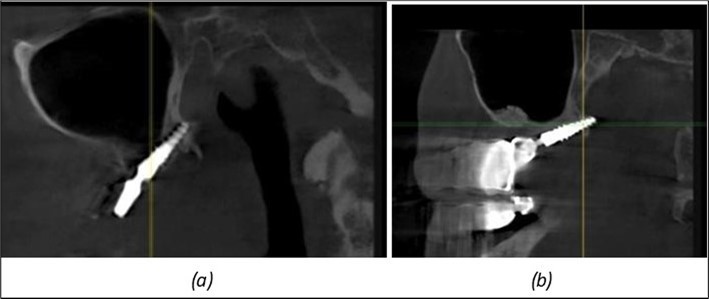

A total of 11 implants is placed in the maxilla, including compressive TPG implants with a polished surface in the maxillary-sphenoid fusion area (Figure 3, Figure 9). Similarly, in the anterior region, final fixation is achieved in the nasal cortex, and BCS corticobasal implants are added in areas with massive bone loss in the frontal region (Figure 3, Figure 8, Figure 11). Additionally, in the palatal sinus cortical area, with the aim of avoiding the addition and sinus lift zone where the second cortical bone no longer exists, 3 implants are placed, 2 in quadrant 1 and 1 in quadrant 2 (Figure 3, Figure 8). Through the Caldwell-Luc sinus lift procedure, the sinus cortical bone is displaced to allow the placement of the graft material and elevation of the sinus membrane. This sinus cortical is no longer recreated at the junction of the graft material and mucosa-sinus membrane, making it impossible to place a corticobasal implant, which relies on the second cortical bone. In the distal mandibular area, after the removal of two stage implants due to massive destruction in quadrant 3, implant placement distal to the mylohyoid line is not possible, as in quadrant 4 (Figure 10). A re-intervention occurs after 5 months to stabilize the area (Figure 12, Figure 14). Also, at the moment of fixation, the tip of one implant fractures, and the decision is made to leave it in place due to regional bone destruction, in order to avoid enlarging the bone defect.

Figure 12.Implants fixed distally in quadrant 4 with fixation at the level of the mylohyoid line: (a) The most distal implant fixed in unaffected bone from the previous restoration; (b) The implant fixed in the area where the two stage implant was removed.